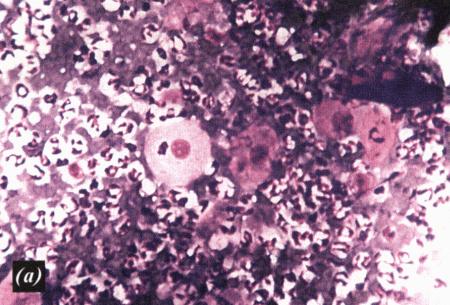

Фиг. 3.9.

Эндометриальные клетки и макрофаги с пенистой цитоплазмой в эндометриальном цитологическом образце, взятом у суки грейхаунда за 46 дней до начала проэструса. Фаза анэструса у этой собаки продолжалась не менее 114 дней (образец окрашен Diff-Quik®) (Воспроизведено с разрешения из Journal of Small Animal Practice (1998) 39, 2–9).